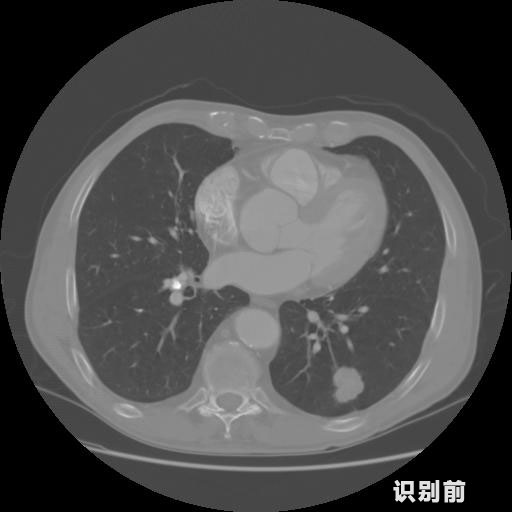

英特健康A(chǔ)I深度學(xué)習(xí)醫(yī)療圖像識別系統(tǒng)案例_胸部CT

1.發(fā)現(xiàn)肺結(jié)節(jié)的可能性為95.56%---位于框指數(shù)位置:[331.70554 366.13406 365.21707 403.96234]